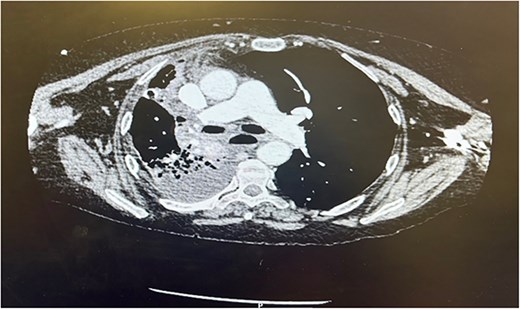

Postoperatively the patient required supplemental oxygen of 4 liters per minute that escalated to high flow nasal canula with 60 liters per minute. A chest x-ray depicted a right sided collection and collapse (Fig. 1). A computed tomography (CT) of the thorax was requested due to concerns from the chest x-ray and increased oxygen demand to maintain patient oxygen saturations between 88–92%. The CT confirmed a right sided moderate collection with secondary collapse and atelectasis of the lung suggestive of postoperative hemorrhagic changes (Fig. 2).

CT thorax Day 3 postoperatively. Right sided pleural effusion with overlying atelectasis and segmental collapse of the right middle and lower lobe.